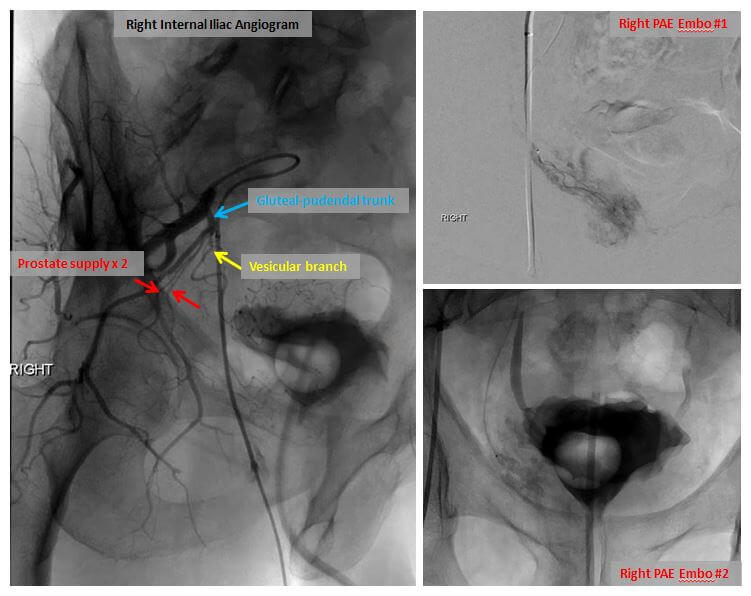

Once the prostatic arteries have been identified, the catheter is repositioned under X-ray guidance and moved into the left prostatic artery. X-ray dye is again injected in order to confirm the position of the catheter. Once this is done, small particles or microspheres are injected into the catheter in order to stop the flow of blood within the left prostatic artery. Once it is injected, the microspheres induce inflammation, slow blood flow, and create clot formation within the artery. When blood flow has stopped within the left prostatic artery, the catheter is repositioned into the right prostatic artery and the procedure is repeated. In our experience, most patients can be embolized with a single catheter entering the arterial system on the right side; a second catheter placed into the left common femoral artery is necessary only in the most difficult cases. Once the embolization is complete, the catheter is removed and a seal is placed into the right common femoral artery to insure that there will be no bleeding from the site. The length of the procedure is variable and highly dependent upon the complexity of the arterial anatomy.

Right internal iliac angiogram demonstrating prostatic arterial anatomy with two arteries supplying the prostate (left image). Embolization images on right.